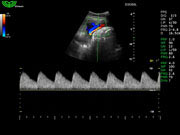

Система поддерживает СFM-режим, PW-режим, CW-режим, режим направленного энергетического потока, режим Color-M, панорамный режим, ECG, DICOM 3.0 и универсальные пакеты программ для кардиологии, сосудистого исследования и акушерства.

Режимы изображения: B, 2B, B/M, B/BC, CFM, PW, HPRF, PD, направленный PD, CW, режим Color M.

Дополнительные возможности: триплекс, трапециидальное отображение, анатомический М-режим, «free-hand» трехмерная реконструкция, авто-доплер.